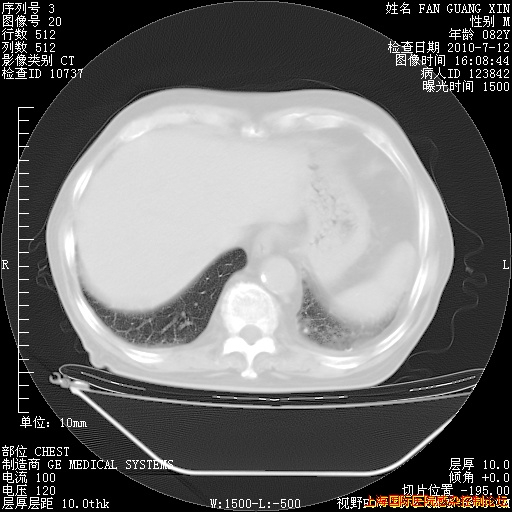

今天复查CT

今天CT

整整相隔30天的肺部CT好像有所好转啊。甲强龙减量第3天,需要观察体温。

海管,自昨日你和我通完话后,不知您岳父消化道症状有无缓解?体温怎样?阅读7.12日胸部ct,个人认为目前激素治疗是有效的,甲强龙减量是适宜的。因在抗痨治疗,需密切观察肝功、肾功能和血常规。不过,老年、长期住院和大量使用激素,很担心菌群失调发生